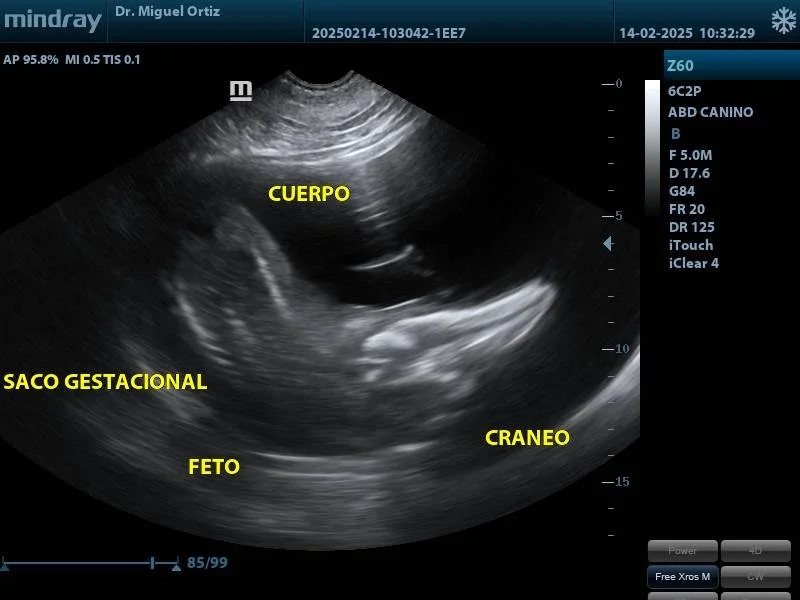

Registro ecográfico de delfín de río hembra, en periodo de gestación. Foto: cortesía MV. Miguel Ortiz